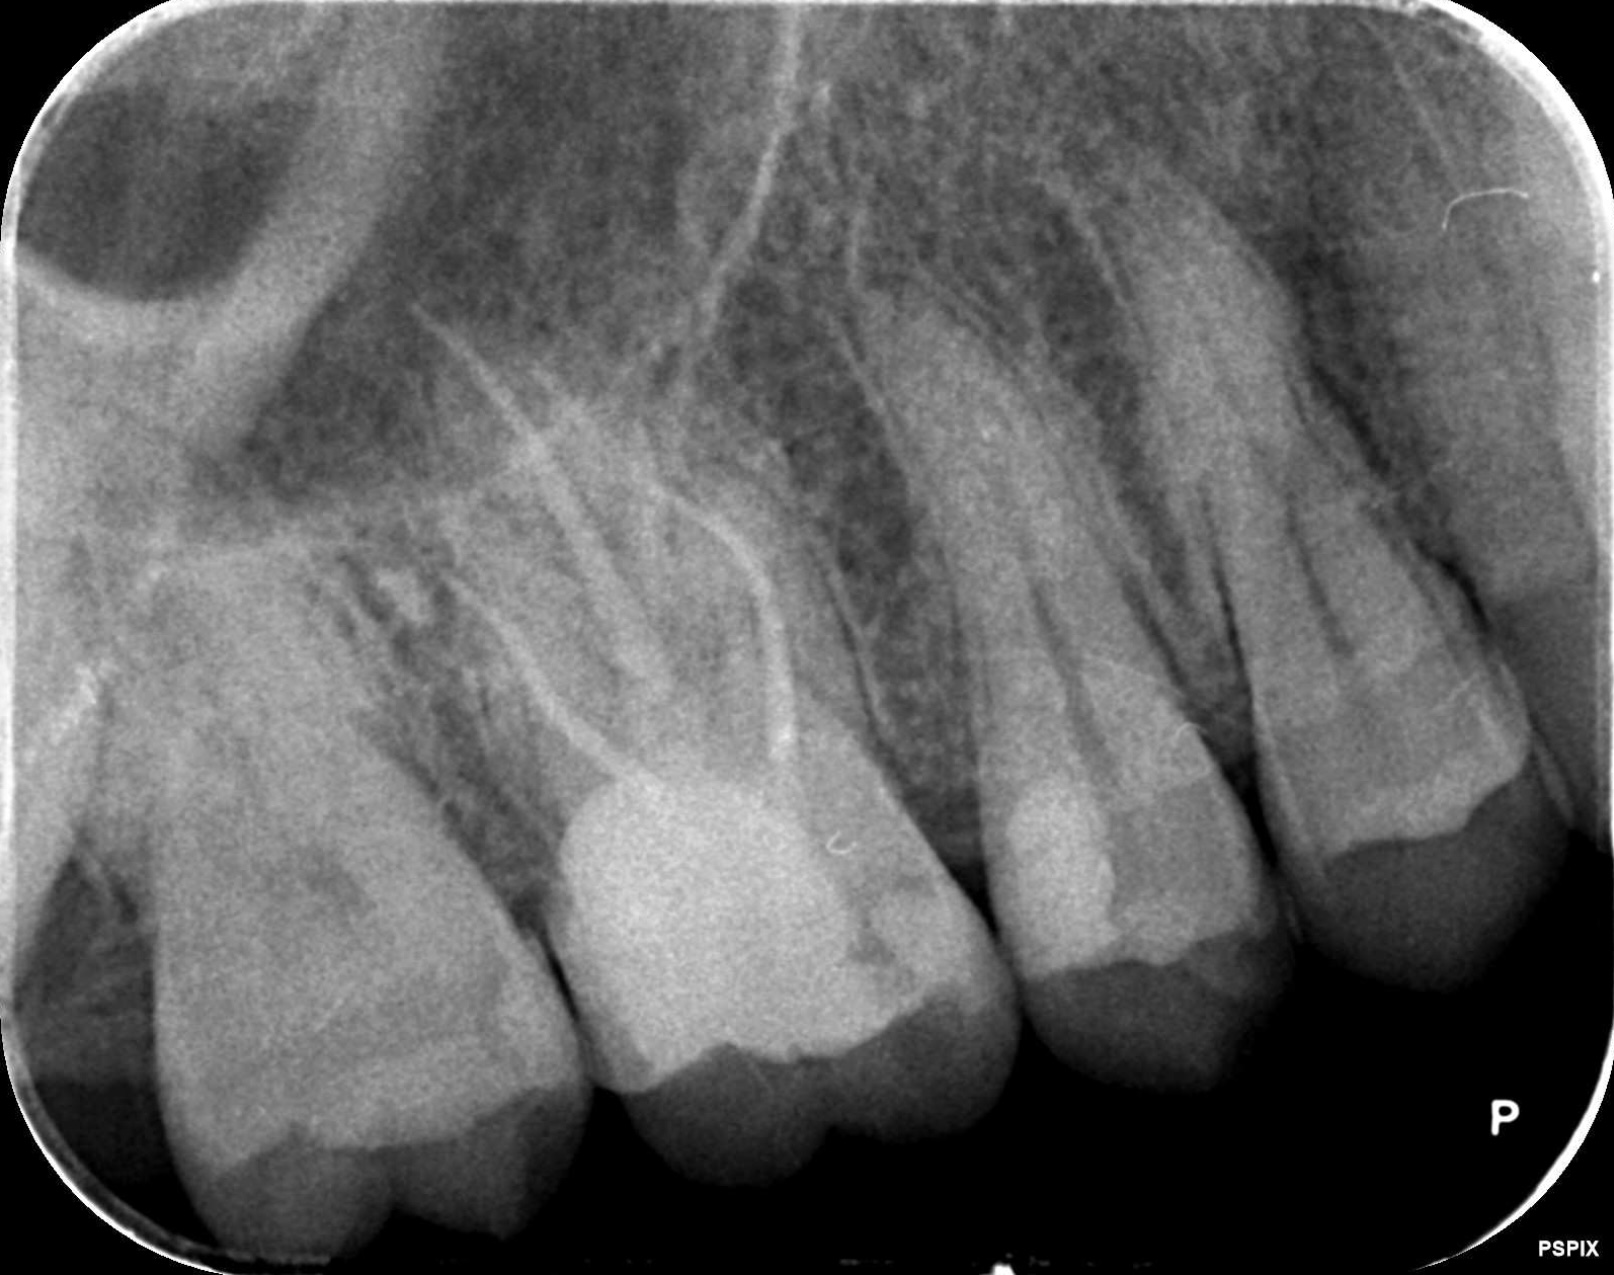

術前

術前画像

持続的な痛みがあり他院で抜歯になると言われて来院されました。右上の奥から2番目の歯に、歯茎を超えて骨の近くまで進行した虫歯を確認いたしました。しっかりと治療方針を説明し患者様の同意を得ました。当院にて歯を抜かない治療を行ないました。